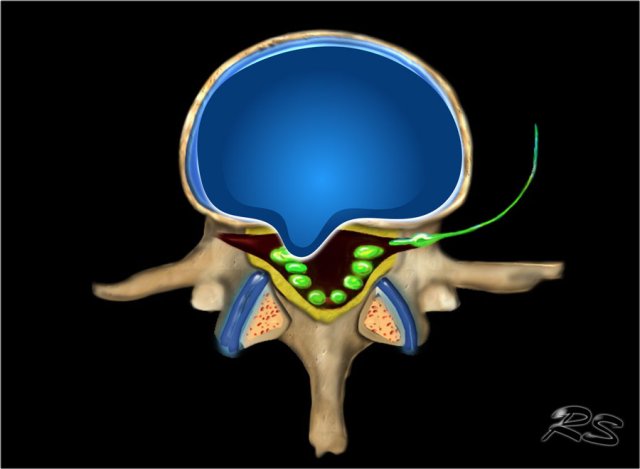

Localization of Herniated Discs

Axial plane

Central

Since the posterior longitudinal ligament (PLL) is at its thickest in this region, the disc usually herniates slightly to the left or right of this central zone.

Subarticular

Because the PLL is not as thick in this region, this is the number one region for disc herniations.

Foraminal

It is rare for a disc to herniate into the intervertebral foramen.

Only 5% to 10% of all disc herniation occur here or farther out.

When herniations do occur in this zone, they are often very troublesome for the patient.

This is because a super-delicate neural structure called the 'Dorsal Root Ganglion' (DRG) lives in this zone resulting in severe pain, sciatica and nerve cell damage.

Extraforaminal

Disc herniations in this region are uncommon.